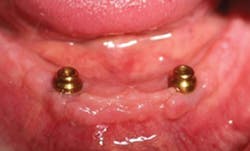

On the day of the procedure, only tooth No. 26 is extracted (figure 4). A full-thickness flap is laid, and implants are placed at site Nos. 23 and 26 just as planned. The final locator abutments are placed and torqued to their final values. A partial denture is fabricated for the patient to wear comfortably during implant integration using the remaining abutment teeth.